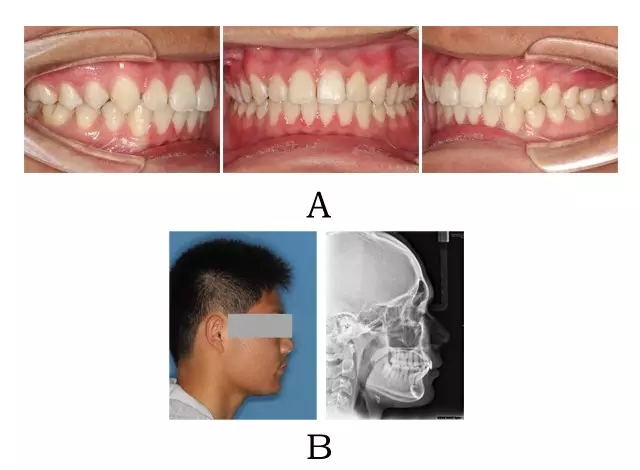

面型前突,面下部高度不足,頦唇溝較深??趦?nèi)表現(xiàn)為上頜骨源性前突,上前牙代償性直立或輕度唇傾;下頜后退伴深覆合深覆蓋,磨牙系遠(yuǎn)中關(guān)系。頭顱側(cè)位片下頜骨體部呈“長(zhǎng)方形”,頦部形態(tài)較好(圖 4-1)。

圖 4-1:混合 I 型突面畸形臨床表現(xiàn)及頭顱側(cè)位影像特征。

(A)齒槽與牙列特點(diǎn) (B)側(cè)貌與影像對(duì)比

Figure 4-1. Clinical manifestation and cephalometric image for merged skeletal and mandibular positional prognathism (Type I). (A) Alveolar and dentition specifics. (B) Facial profile and radiographic image.